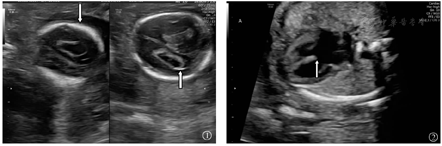

本组175例中孕期18-TS胎儿中,169例(96.6%)的胎儿超声表现异常,其余6例(3.4%)未见异常。超声表现异常胎儿中,157例(89.7%)异常≥2项。在结构异常胎儿中,心脏畸形(131例、74.9%),肢体畸形(113例、64.6%),面部畸形(90例、51.4%)与中枢神经系统异常(60例、34.3%)最为常见。超声软指标异常胎儿中,脉络丛囊肿(116例、66.3%)(图1)最为常见,其次为单脐动脉(54例、30.9%)。非特异性超声异常胎儿中,羊水过多(13例、7.4%)与宫内生长受限(11例、6.3%)最为常见。本组175例中孕期18-TS胎儿超声表现,见表1。

本组175例中孕期18-TS胎儿最常见超声结构异常(心脏、肢体、面部畸形及中枢神经系统异常)胎儿中,心脏畸形以室间隔缺损最为常见(70例、40.0%),其次为心内膜垫缺损(28例、16.0%)(图2);肢体畸形以钩状手(第3、4指紧贴手掌,第2、5指压在其上)最为常见(35例、20.0%)(图3),其次为重叠指(28例、16.0%);面部畸形以小下颌(43例、24.6%)最为常见;中枢神经系统异常以草莓头(33例、18.9%)(图4)最为常见。本组175例中孕期18-TS胎儿最常见超声结构异常心脏、肢体、面部畸形及中枢神经系统异常分布情况,见表2。

18-TS胎儿多伴有解剖结构异常,并且表现为多发畸形[19]。本组175例中孕期18-TS胎儿超声检查结果显示,157例(89.7%)异常≥2项,最常见为心脏畸形(131例、74.9%),心脏畸形中又以室间隔缺损最为常见(70例、40.0%),其他特征性表现包括钩状手(35例、20.0%),小下颌(43例、24.6%),草莓头(33例、18.9%)。虽然18-TS胎儿四肢畸形较常见,但是受胎儿体位、羊水、产前超声检查医师经验不足等限制,中孕期超声检查对该类畸形漏诊率较高[24]。因此,中孕期超声检查发现胎儿存在其他部位畸形时,更应重点观察其肢体,发现草莓头、小下颌、钩状手、脉络膜囊肿、心脏畸形等特征性超声异常及多发异常时,应高度警惕18-TS。对于中孕期超声检查发现异常≥2项的胎儿,建议对其进行遗传学咨询,必要时进行染色体核型分析。

越来越多研究发现超声软指标异常,即微小异常指标,在胎儿结构发育检测方面有独特应用价值[25]。本组175例18-TS胎儿中,最常见超声软指标异常为脉络丛囊肿(116例、66.3%),仅次于心脏畸形,这与Cheng等[26]研究结果一致。正常妊娠胎儿脉络丛囊肿发生率为1%~2.5%,一般于胎龄>22周时,该症状可逐渐消失,若动态观察至胎龄为26周时,该症状仍未消失,或合并其他超声软指标异常,应对此类胎儿进行产前诊断[27,28]。因此,若中孕期超声检查发现胎儿脉络膜囊肿,临床应提高警惕,详细筛查胎儿其他结构,尤其注意是否合并心脏畸形与肢体畸形。中孕期超声检查和辨识超声特征,可提高18-TS高风险胎儿检出率,避免不必要的有创检查,降低18-TS胎儿出生率[1,29,30]。